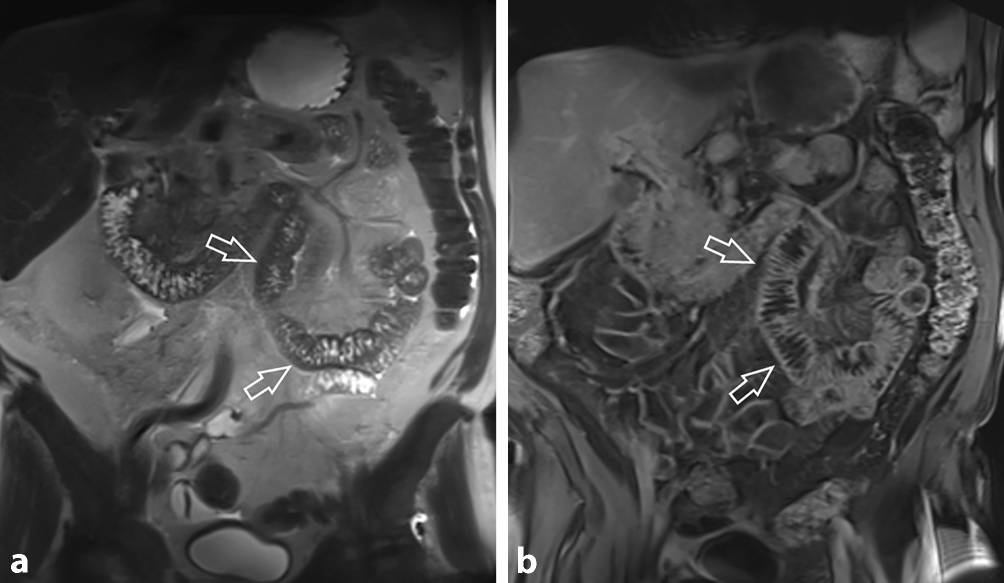

Ein 67 Jahre alter Patient mit bekannter Leberzirrhose (Child-Pugh Score A, MELD 11) wurde aufgrund seit zirka 10 Tagen bestehenden diffusen Bauchschmerzen stationär aufgenommen. Bekannt waren auch dank einer rezenten Gastroskopie das Vorliegen von Ösophagusvarizen und inzipienten Fundusvarizen. Der Patient wurde zur weiteren Abklärung zu einer kontrastmittelverstärkten Multidetektor-CT (MDCT) zugewiesen, welche eine ausgeprägte Thrombose sowohl der intra- und extrahepatischen Pfortader, der V. mesenterica superior und der V. lienalis zeigte (Abb. 1). Überdies zeigte sich aufgrund der ausgedehnten Thrombose eine Splenomegalie und auch Aszites. Aufgrund fehlender Zeichen einer Darmischämie wurde von einer chirurgischen Intervention abgesehen, es wurde stattdessen eine therapeutische Antikoagulation mit niedermolekularem Heparin und in weiterer Folge Apixaban eingeleitet. Die Abklärung hinsichtlich einer zu Grunde liegenden Gerinnungsstörung brachte kein Ergebnis, es fand sich auch keine Neoplasie. Im weiteren Verlauf kam es zum Auftreten von Melaena. In der daraufhin durchgeführten Gastroskopie fand sich kein Hinweis auf eine Blutung. Die MDCT-Verlaufskontrolle zeigte eine ausgeprägte Verdickung der proximalen Jejunumschlingen, mit Zeichen petechialer Einblutungen (Abb. 2). Die Kontrastmittel-MDCT zeigte auch eine Abgangsstenose des Truncus ceoliacus mit poststenotischer fusiformer Ektasie bei Vorliegen eines Ligamentum arcuatum. Allerdings zeigten sich keine Kollateralen zwischen Tr. coel. und A. mes. sup., was eine hämodynamisch signifikante Stenose weitgehend ausschloss. Zum Ausschluss einer paraneoplastischen Mesenterialvenenthrombose wurde nach dem Kontrastmittel-MDCT, der Gastro-Duodenoskopie und der Colonoskopie noch eine MR-Enterographie zwei Wochen später durchgeführt, welche keinen Hinweis auf einen Tumor im Dünndarm ergab, jedoch die Rückbildung des Dünndarmödems zeigte (Abb. 3). Aufgrund der bekannten und nur partiell rekanalisierten Thrombose von Pfortader, V. mes. sup. und V. lienalis zeigte sich auch eine progrediente Splenomegalie. Eine diagnostische Aszitespunktion erbrachte keine weiteren Erkenntnisse. Unter adäquater Schmerztherapie und Anpassung der internistischen Therapie konnte eine deutliche Besserung des Allgemeinzustandes erreicht werden. Die weiterführende laborchemische Abklärung der incipienten Leberzirrhose war unauffällig, sodass eine Leberbiopsie im Rahmen eines Folgeaufenthaltes geplant wurde.

Abb. 3

Die MR-Enterographie nach weiteren 2 Wochen (a T2-gew. Sequenz; b Kontrastmittelserie) zeigt eine Rückbildung des Darmwandödems (offene Pfeile) und des Aszites